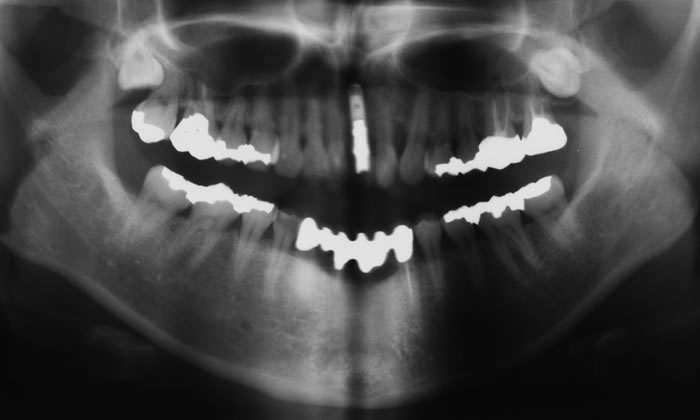

• インプラントパノラマ写真

治療後のレントゲン写真です。